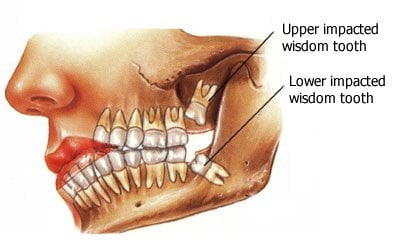

1.The Wisdom Teeth

Our ancestor’s diet comprised of many raw plants, which had to be eaten faster than we do today. This was because they had to ingest a lot of this material in a single day to compensate for the lack of nutrient variety. The extra set of molars, i.e., the Wisdom Teeth, helped in this faster chewing process and made eating more efficient.

As evolution made its selection, however, our anatomy changed, our diets grew appropriately smaller, and our need to process food faster was reduced. Some people don’t even develop Wisdom Teeth, further proving their uselessness.